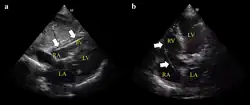

The pacing device may also be advanced through the vein under electrocardiography (ECG) or ultrasound guidance.[1][3] Before pulling back the device make sure the balloon is deflated.[2]

Ultrasound showing the device in the right ventricle -

Example of ECG off the device a) free floating in the RV b) in contact with the RV wall -